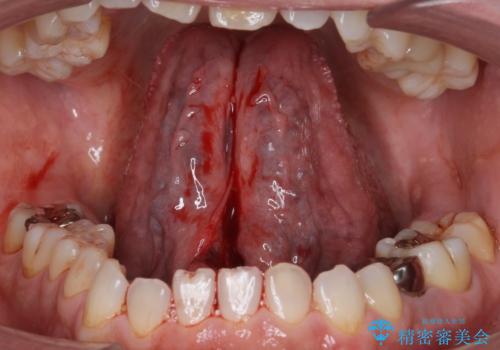

局所麻酔下にて施術しました。

術後1週間で抜糸、約2週間で完全に治癒していきました。

切除後は特にラ行が言いやすくなったそうで大変喜んでいただけました。